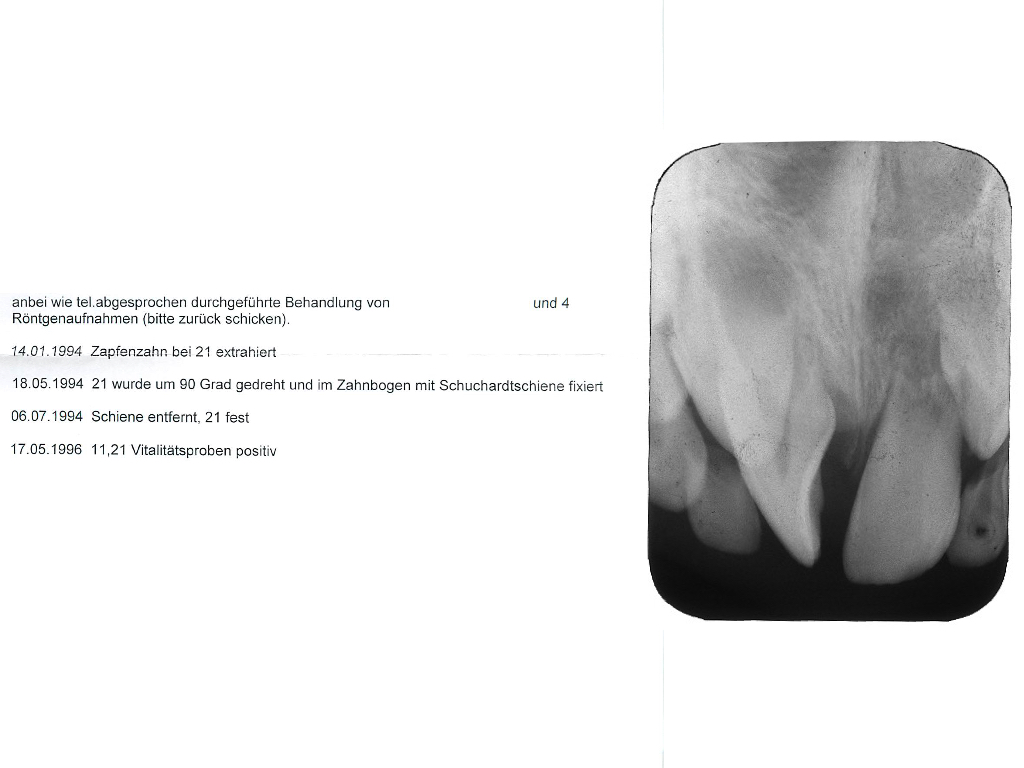

Röntgenbefund.002

Röntgenbefund (2)